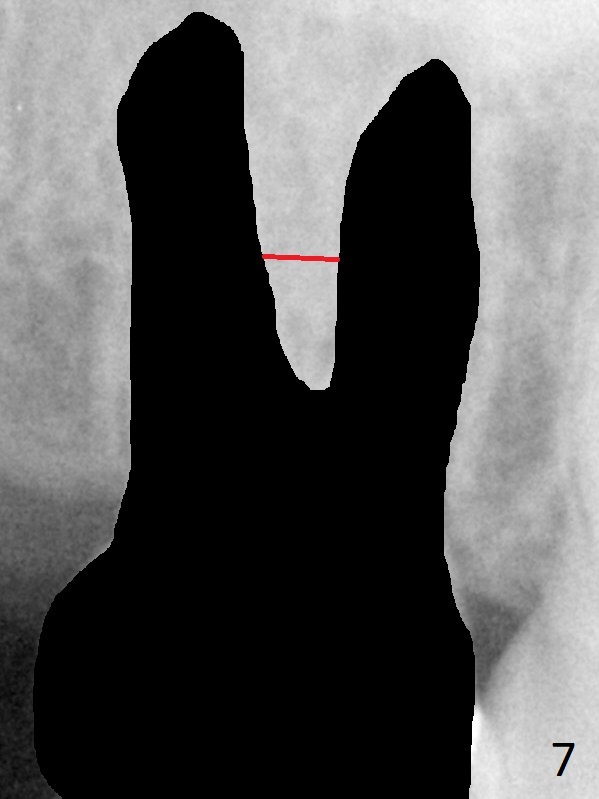

A 58-year-old woman has had RCT done at #2 for several years. The roots are trifurcated with sufficient bone height (Fig.1-3). Recently the tooth becomes symptomatic with formation of a distal fistula (Fig.4). After extraction, the septum (Fig.5 S) may be wide enough for initial drill (Fig.6). If not, resection the thin part of the septum (Fig.7 red line, with small or medium Rongeur) and use the initial drill (Fig.8). Anyway, take PA immediately to avoid sinus membrane perforation. If possible, adopt single drill technique.